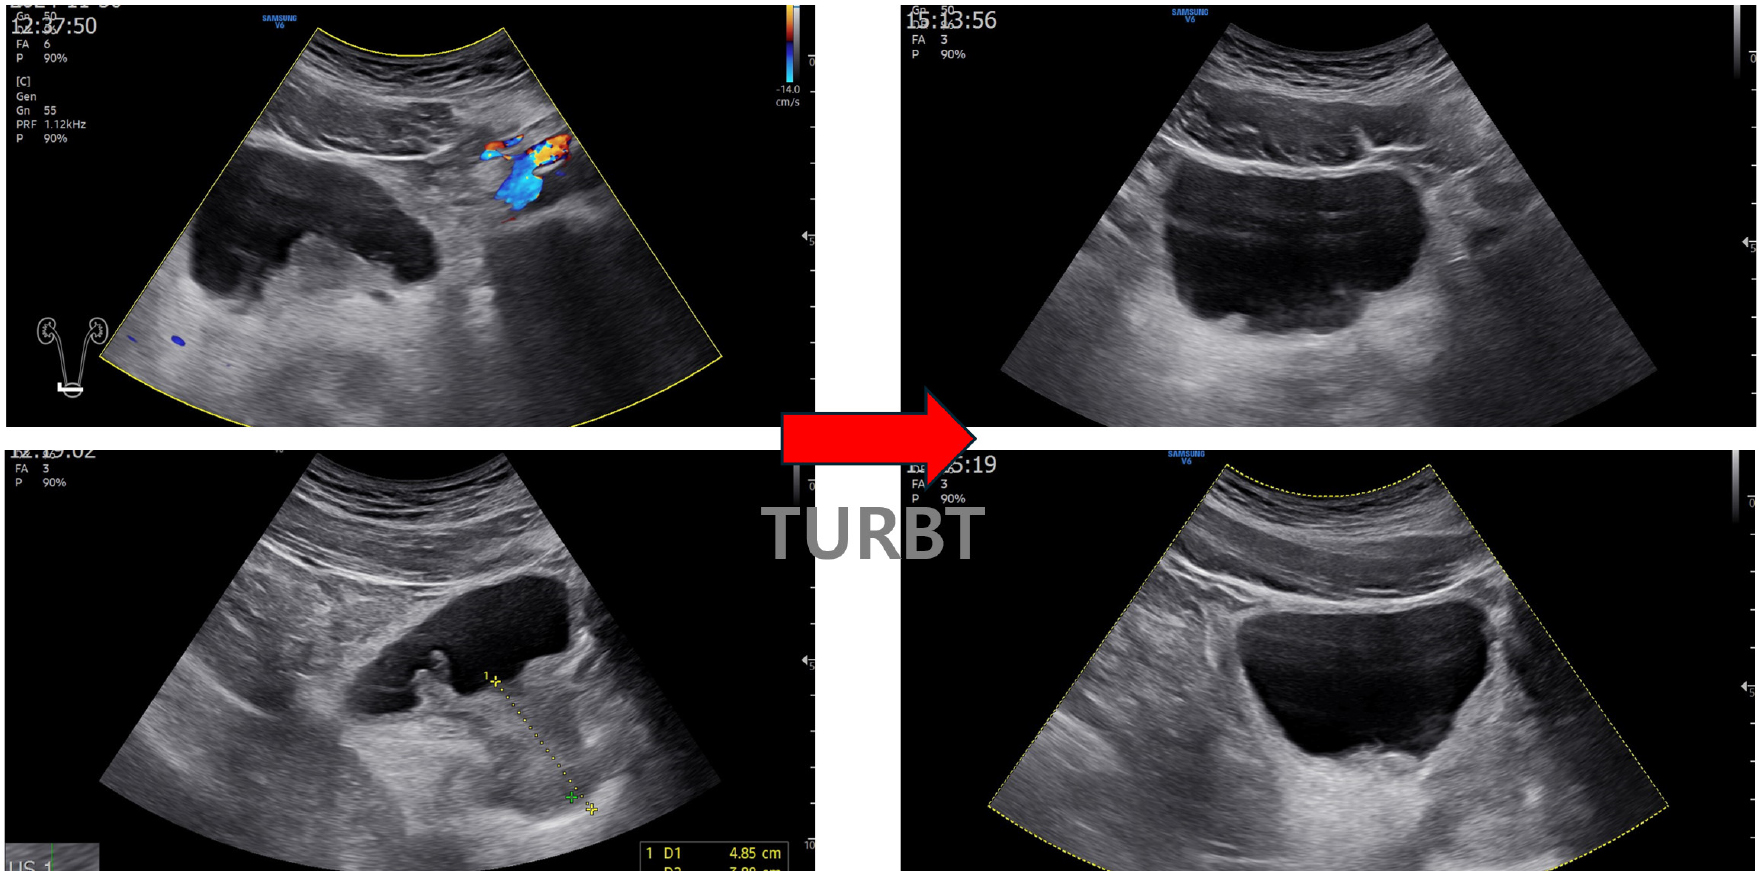

▶ 경직장 전립선 초음파 및 신장 및 부신 방광 초음파

환자의 전립선 상방으로 폴립형 종물(polypoidal mass)이 확인되었으며, 3*4 cm 범위로 방광목에서 방광삼각부(bladder trigone)에 걸쳐 분포하였다. 전립선의 크기는 30 cc로 혈류의 증가 소견이 있었다. 양측 신장은 장축 10 cm 크기로 정상이었으며 수신증 등 이상 소견은 확인되지 않았다.

환자는 1일 입원 후 퇴원하였으며, 수술 후 3일째 혈뇨 및 좌측 옆구리 통증 소견으로 타원(2차 병원) 입원하여 방광 세척 및 경과관찰 후 퇴원하였다. 2주 경과하여 본원 내원하였으며 ipss는 8점(1105001-1)로 이전보다 저장 및 배뇨 증상이 호전되었으며, 야간뇨는 1회 이하로 줄었다. 이전처럼 배뇨 시 소변이 끊기는 증상이 호전되어 만족감이 있었다. 수술 2개월 후 시행한 방광 및 신장 초음파 검사에서 방광저 부위(base of the bladder)는 깨끗해졌고 약간의 비후 및 불규칙 소견은 보였으며, 양측 요관 확장 및 수신증 소견은 없었다.